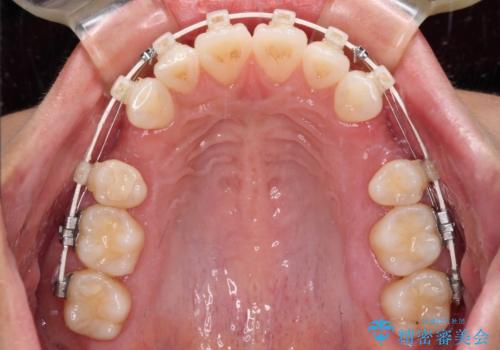

- 矯正装置

- 審美装置

- 飛び出した前歯を気にして来院された患者様です。

口元を引っ込めるために上下左右の第一小臼歯4本を抜歯することとしました。

結婚式を行う予定があるとのことで、表側のワイヤー装置で、速やかに治療を終えられるようにしました。

途中妊娠と出産がありましたが、予定よりも早く治療を終えることができました。